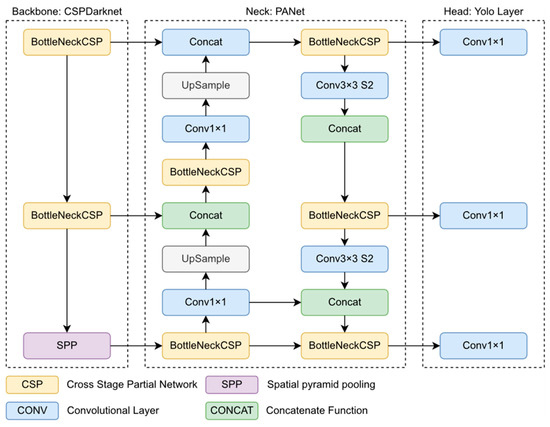

英文标题: One-Stage Methods of Computer Vision Object Detection to Classify Carious Lesions from Smartphone Imaging

中文标题: 基于单阶段计算机视觉目标检测的智能手机影像龋损识别方法

文章链接:https://www.mdpi.com/2673-6373/3/2/16